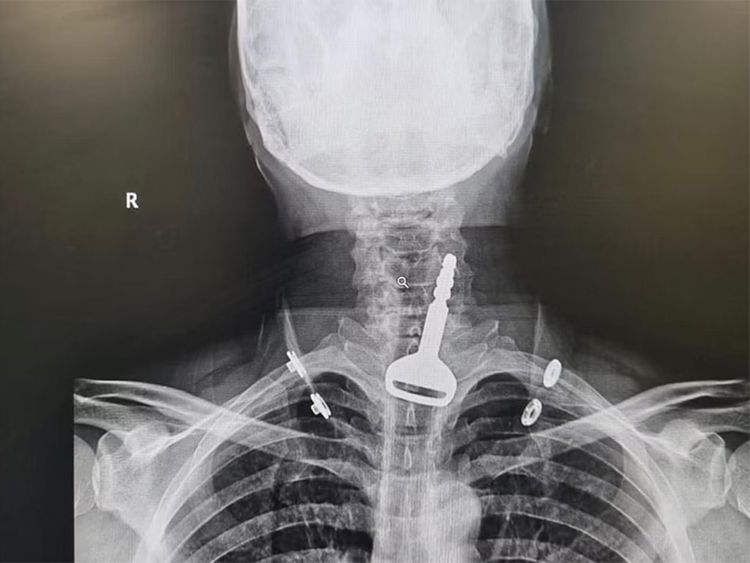

据当地新闻报道,这名49岁的男子被送往医院的急诊室,医护人员注意到他呼吸困难。X光检查显示呼吸通道内有一把车钥匙,患者告诉医生,他在玩闹时不小心吞下了它。之后医生决定用内窥镜检查,以移除钥匙并清除气道阻塞,但该男子是心脏病患者,这让手术变得更加复杂。

幸运的是,腹腔镜手术成功,车钥匙也被找回。病人住院了几天,以确保没有并发症,目前已出院了。